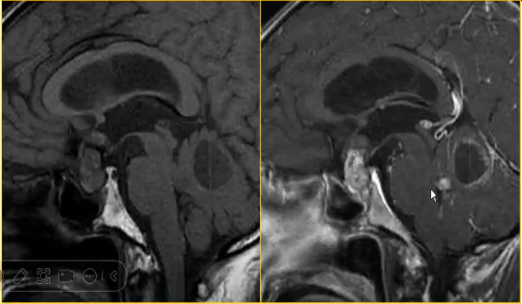

√ 神经鞘瘤:有包膜,常伴各种退变:粘液样变、脂肪变性、色素沉着;囊实性,粘液于裂隙状分布于实质中,包膜下囊变是特征